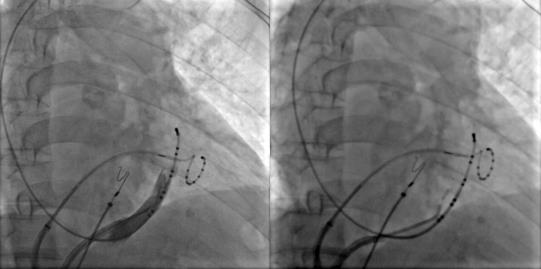

冠狀竇造影定位Marshall靜脈,應用OTW球囊進行酒精消融

Marshall靜脈酒精消融完成后進行左房標測提示二尖瓣峽部徹底隔離,酒精消融成功,接著進行三尖瓣峽部消融后患者房撲轉(zhuǎn)為竇性心律,完美完成此次房顫的消融手術(shù)。